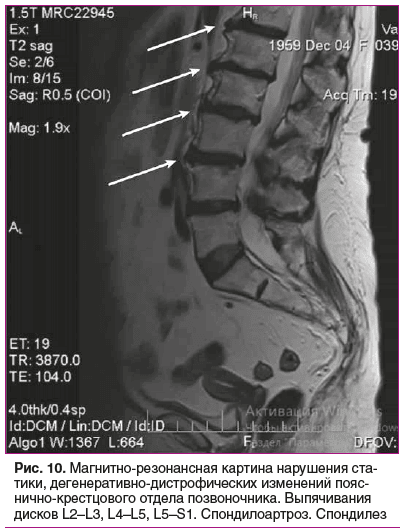

Данные инструментальных методов исследования. Магнитно-резонансная томография (МРТ) пояснично-крестцового отдела позвоночника (рис. 10): множественные протрузии межпозвонковых дисков в пояснично-крестцовом отделе позвоночника, заострения тел позвонков с краевыми костными разрастаниями по передней и боковым поверхностям тел L1-S1-позвонков. МР-картина нарушения статики, дегенеративно-дистрофических изменений пояснично-крестцового отдела позвоночника. Выпячивания дисков L2–L3, L4–L5, L5–S1. Спондилоартроз. Спондилез.

Диагноз. Синдром Элерса — Данло артрохалазийного типа с врожденным двусторонним вывихом бедер и двусторонним эндопротезированием в 2001 г., двусторонним коксартрозом, R-стадия 4, функциональная недостаточность сустава III, дистальной аксональной и демие-линизирующей полинейропатией, легким тетрапарезом, гипермобильностью мелких и средних суставов (6 баллов по Бейтону — Хорану в 65 лет), гиперрастяжимостью, ранимостью, атрофией кожи на конечностях — акрогерией. Дегенеративно-дистрофические изменения пояснично-крестцового отдела позвоночника (L1-S1), множественные протрузии межпозвонковых дисков в пояснично-крестцовом отделе позвоночника L2–L3, L4–L5, L5–S1. Спондилоартроз. Спондилез. Хронический болевой синдром. Синдром хронической тазовой боли с нарушением функции тазовых органов (задержка мочеиспускания и дефекации при отсутствии рефлексов). Манубриостернальный тип килевидной деформации грудной клетки, гиперлордоз и сколиоз влево поясничного отдела позвоночника, поперечное плоскостопие, hallux valgus, рецидивирующая бедренная грыжа (герниопластика в 2007 г.), моллюскоподобная опухоль передней брюшной стенки, пьезогенные папулы пяток. Резистентная к терапии ГЭРБ, частично корригированная операцией фундопликации по Ниссену в 2024 г. Остеопения (Т-критерий 1,7), патологические переломы костей предплечья справа и тел позвонков. Тромбоцитопатия с нарушениями гемостаза (наклонность к геморрагиям и повторные тромбозы, спонтанные или после операций). Гипертоническая болезнь 2-й степени, I стадии, риск 3 (высокий). Целевой уровень АД не достигнут. Хроническая обструктивная болезнь легких. Ожирение 1-й степени (ИМТ 32,9 кг/м2). Множественная аллергия на лекарства (новокаин, лидокаин, витамины группы В, пенициллины, цефалоспорины, сульфаниламиды, ингибиторы АПФ, β-адреноблокаторы, ибупрофен) — крапивница или отек Квинке.